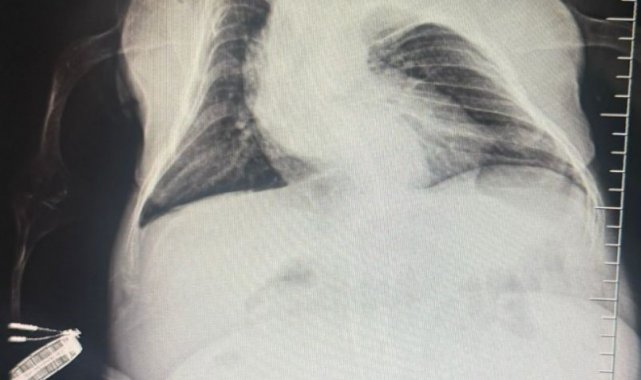

Anestezi Doktoru Mahmut Gül, "Hastamız 30 yaşında. 80 santimetre boyunda, 24 kilo ağırlığında bir kardeşimiz. Kendisinin yumurtalıklarında kist olduğu için ameliyat olması gerekti. Biz bu ameliyatta hastamıza önce büyük bir damar yolu açtık kasıktan. Çünkü damar yolunun çok önemi var ve daha sonrasında ameliyat sırasında belinden uyuşturduk ve ameliyatı sorunsuz bir şekilde belden uyuşturmayla hastamız uyanık bir şekilde tamamladık. Hastadan 3 kilo kist çıktı. Öncesinde 24 kilo olan hastamız, ameliyat sonrasında 21 kiloyla şifalı bir şekilde serviste yatıyor. Ameliyatı bugün oldu. Şu anda da serviste hastamız. Bu tür ameliyatlarda uyutmak hastamız açısından oldukça risklidir. Biz o yüzden bölgesel anesteziyi yani belden uyuşturmayı tercih ettik. Literatürde çok olmayan bir hasta ve güvenli bir şekilde hastanemizde bu ameliyat tamamlandı" dedi.

Kadın Hastalıkları Uzmanı Mustafa Kır, "Hastamızda 20 santimlik tümör vardı kistlik yapıda. Onu başarılı bir operasyonla çıkarttık" şeklinde konuştu.